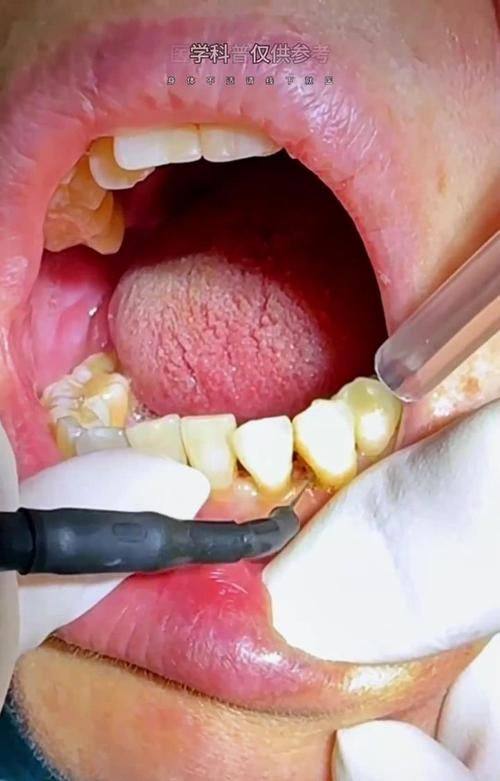

牙周病治疗:拥有专精的牙周诊疗团队,采用规范的治疗流程,结合精良设备,能有效控制牙周炎症,改善牙周健康状况,帮助患者解决牙龈出血、牙齿松动等牙周问题。